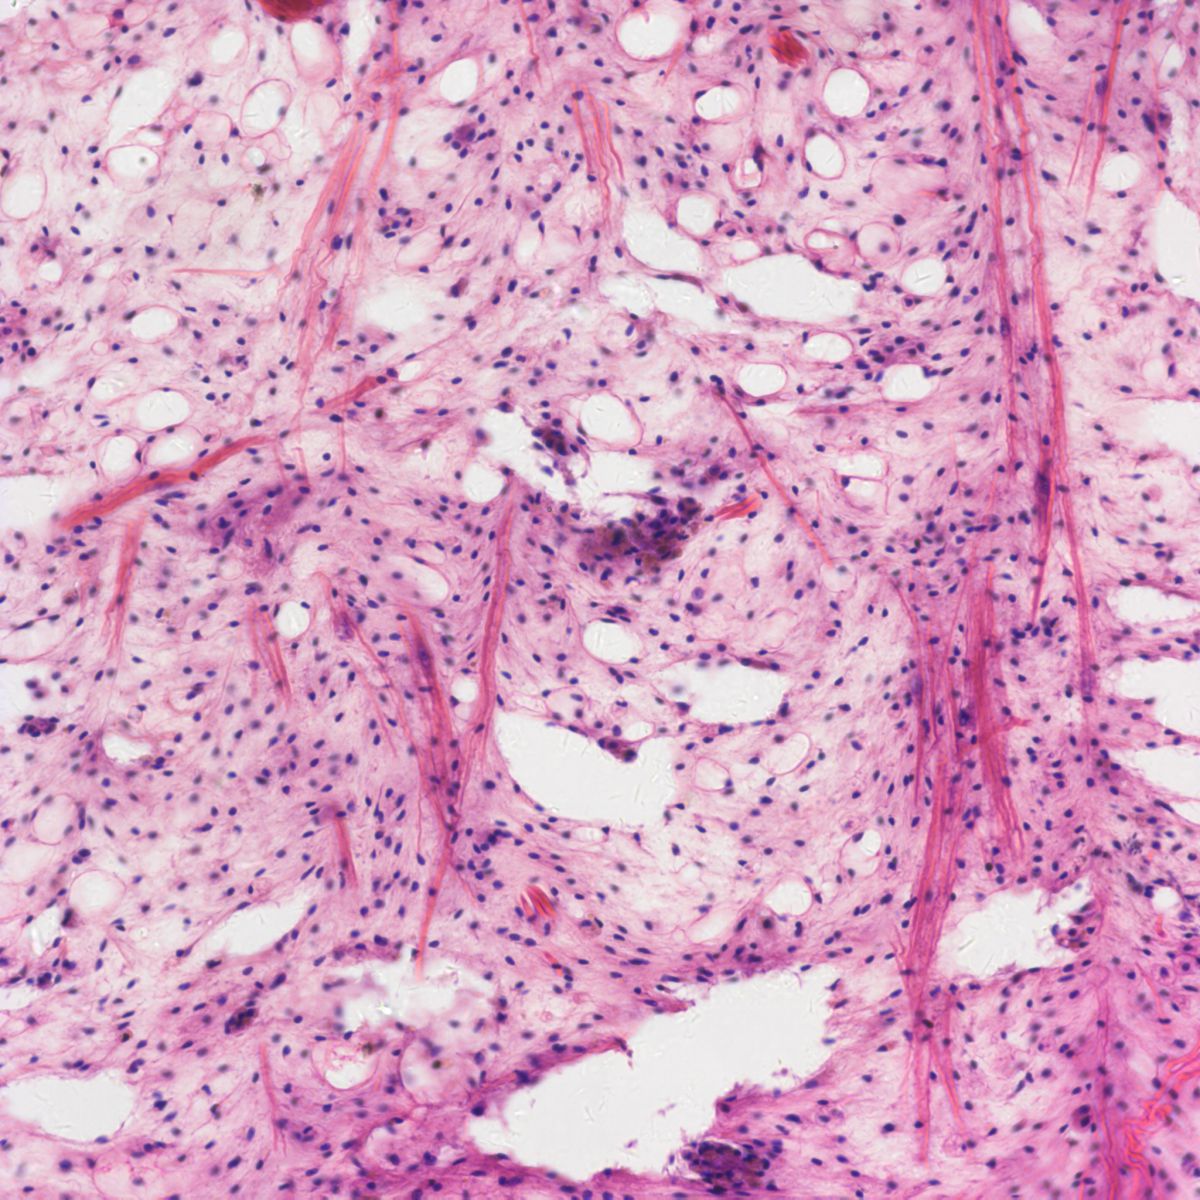

病理圖像分析對數碼成像的藍\紫\紅色提出了很高的要求,400DC在這些區域的完美表現,可以為病理分析判斷提供可靠的依據。

400DC科研級的靈敏度大大拓展了各類熒光成像的應用需求,完美色彩還原用于獲取高色彩還原性的明場圖像,為您帶來科學影像迄今最高品質的色彩應用體驗!

400DC應用圖欣賞